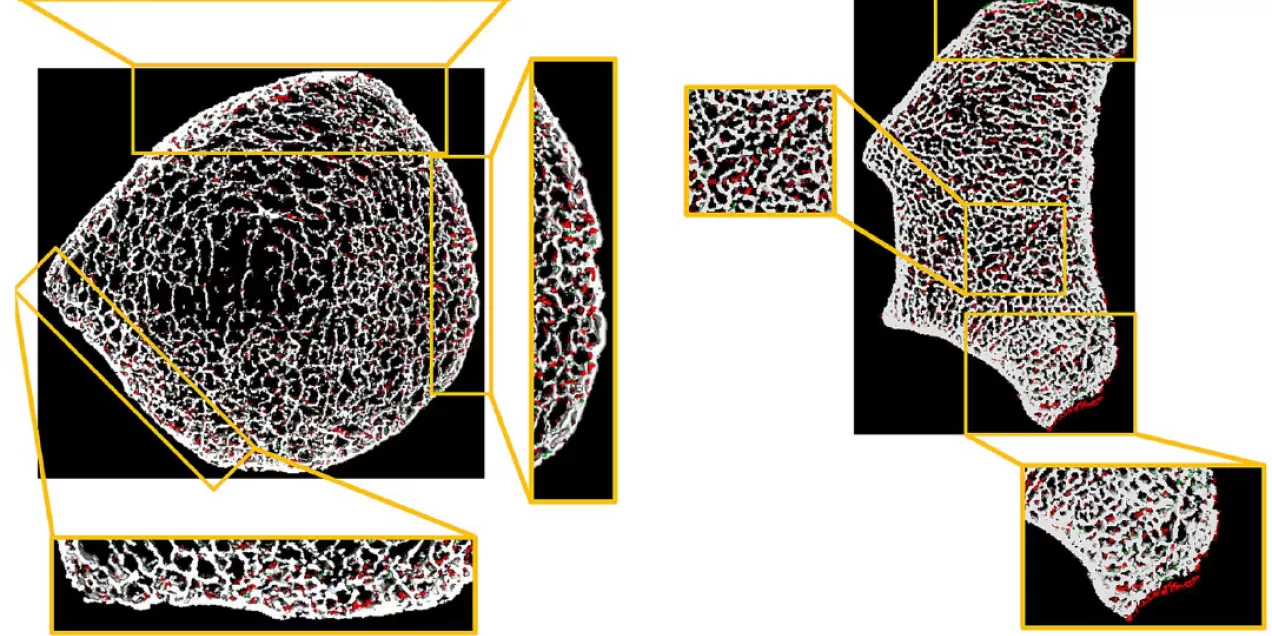

HR-pQCT is a non-invasive and low radiation dose imaging modality that acquires very high-resolution images of bone morphologic features. By comparing two time-lapse images produced by the newest generation of HR-pQCT scanners, the time-lapse analysis can evaluate temporospatial bone gain and loss, producing a ‘virtual bone biopsy.’ This study evaluated the application of this time-lapse HR-pQCT technique to assess and monitor local bone formation and resorption in patients with CKD.

Kazakia, Zhou, and their colleagues found that with just two months between HR-pQCT scans, the time-lapse HR-pQCT pipeline was able to reliably assess local bone turnover in a cohort of patients with end-stage kidney disease. Their findings show that time-lapse HR-pQCT holds promise as an effective and painless ‘virtual bone biopsy’ that reliably assesses and monitors local bone turnover for CKD bone care.